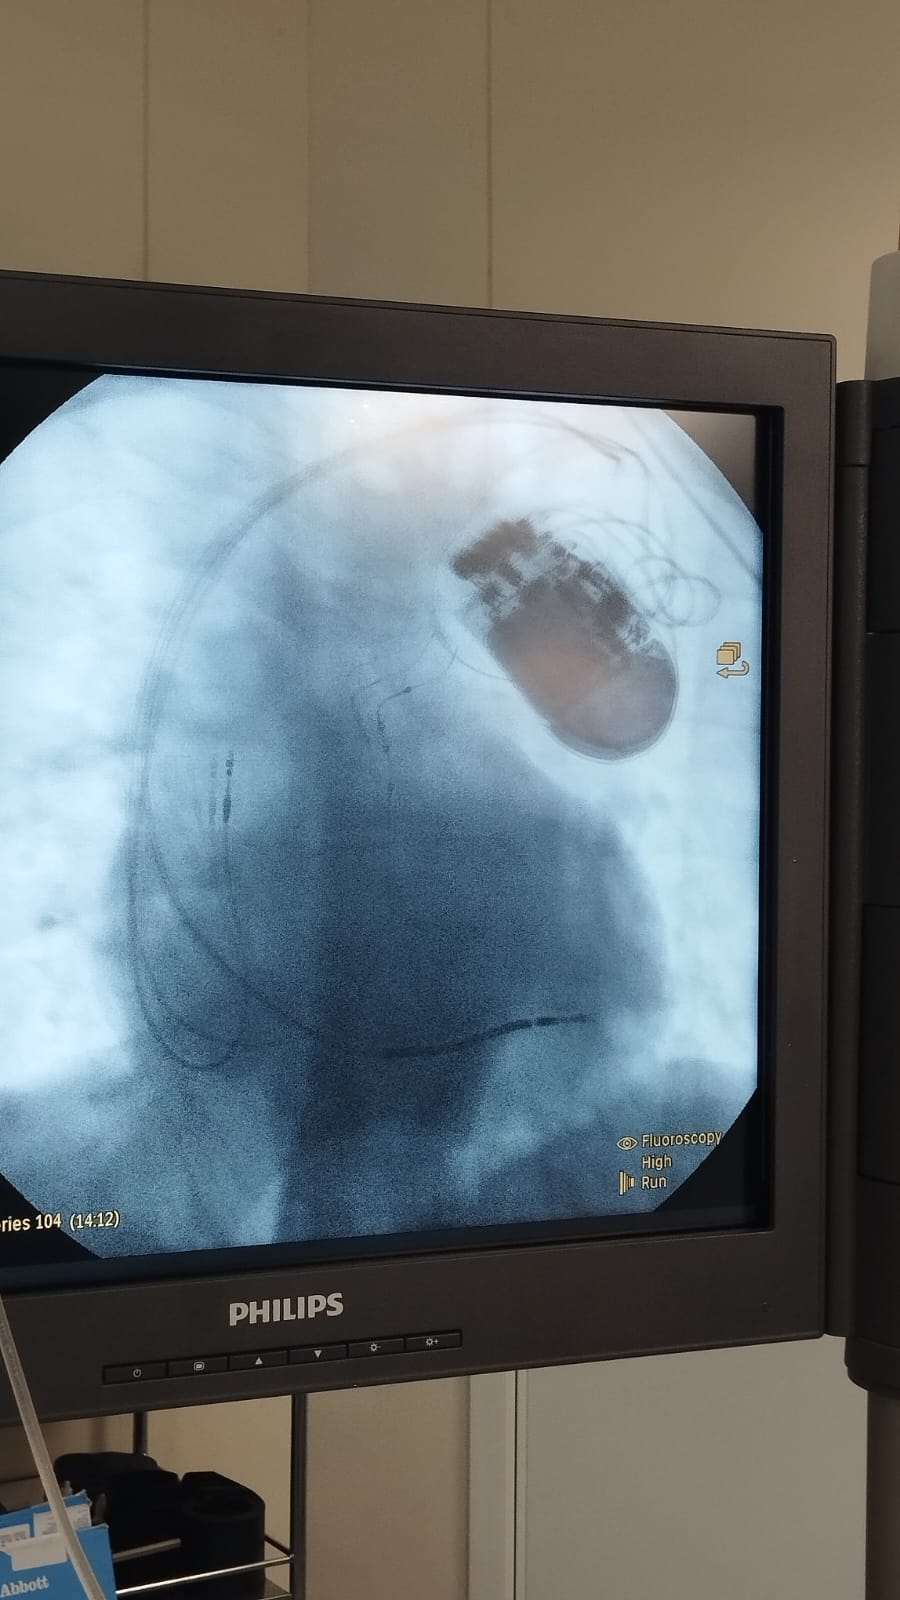

O Hospital Regional do Litoral Norte – Francine Maia França (HRLN) realizou, pela primeira vez, o implante de um cardiodesfibrilador multissítio com marca-passo ressincronizador dupla câmara. O procedimento inédito na unidade amplia o acesso da população do Litoral Norte de São Paulo a tratamento cardíaco de alta complexidade, reduzindo a necessidade de encaminhamento para outros centros. O paciente, de 73 anos e morador da região, apresenta boa evolução clínica e segue em acompanhamento ambulatorial.

O equipamento combina duas funções essenciais: atua como desfibrilador implantável, capaz de identificar e corrigir arritmias potencialmente fatais por meio de estímulos elétricos, e como sistema de terapia de ressincronização cardíaca, que melhora a coordenação dos ventrículos e torna o bombeamento do sangue mais eficiente.